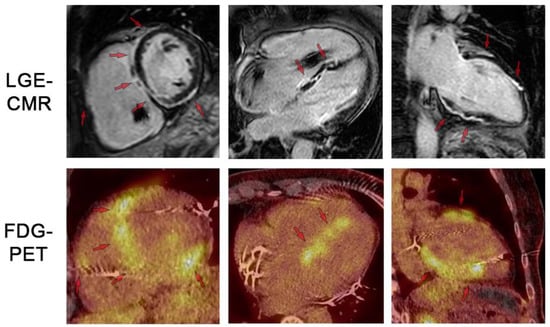

3.1. Advanced Imaging: Cardiovascular Magnetic Resonance (CMR)

3.2. Advanced Imaging: FDG-PET